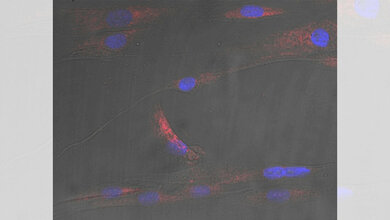

„Extrazelluläre Vesikel sind kleine membranumhüllte Partikel, die aus allen Körperzellen freigesetzt werden und eine Art Momentaufnahme des zellulären Geschehens durch den Körper tragen. Man kann sie mit Trojanischen Pferden vergleichen, die Proteine, Lipide und Nukleinsäuren zu einem Zielgewebe transportieren und dort freisetzen. In der neuen Zelle angekommen, können sie deren Funktion verändern“, erklärt Konxhe Kulaj, Doktorandin und Erstautorin der Studie. „So gelangen extrazelluläre Vesikel aus den Fettzellen gezielt zu den Betazellen der Bauchspeicheldrüse, werden dort aufgenommen und steigern dort die Ausschüttung des Hormons Insulin“ führt Kulaj weiter aus.

Zusammen mit ihrer Mit-Doktorandin Michaela Bauer, ihrer Kollegin Dr. Alexandra Harger und mit Hilfe der Proteom-Forscherinnen Dr. Natalie Krahmer und Özüm Sehnaz Caliskan von Helmholtz Munich konnte sie in einer Reihe von Versuchen nachweisen, dass extrazelluläre Vesikel aus gesundem und adipösem Fettgewebe eine sehr unterschiedliche Zusammensetzung an Botenstoffen als „Fracht“ mit sich führen und dadurch die Funktion von Betazellen der Bauchspeicheldrüse verschiedenartig beeinflussten. Stammten die extrazellulären Vesikel aus gesundem Fettgewebe, wie es bei Normalgewicht vorliegt, wurde die Insulinausschüttung nur geringfügig verändert. Extrazelluläre Vesikel aus adipösem Fettgewebe übertrugen dagegen spezifisch Proteine und Nukleinsäuren auf die Bauchspeicheldrüse, die dort die Freisetzung von Insulin stark erhöhten. In Folge sanken die Blutzuckerspiegel.